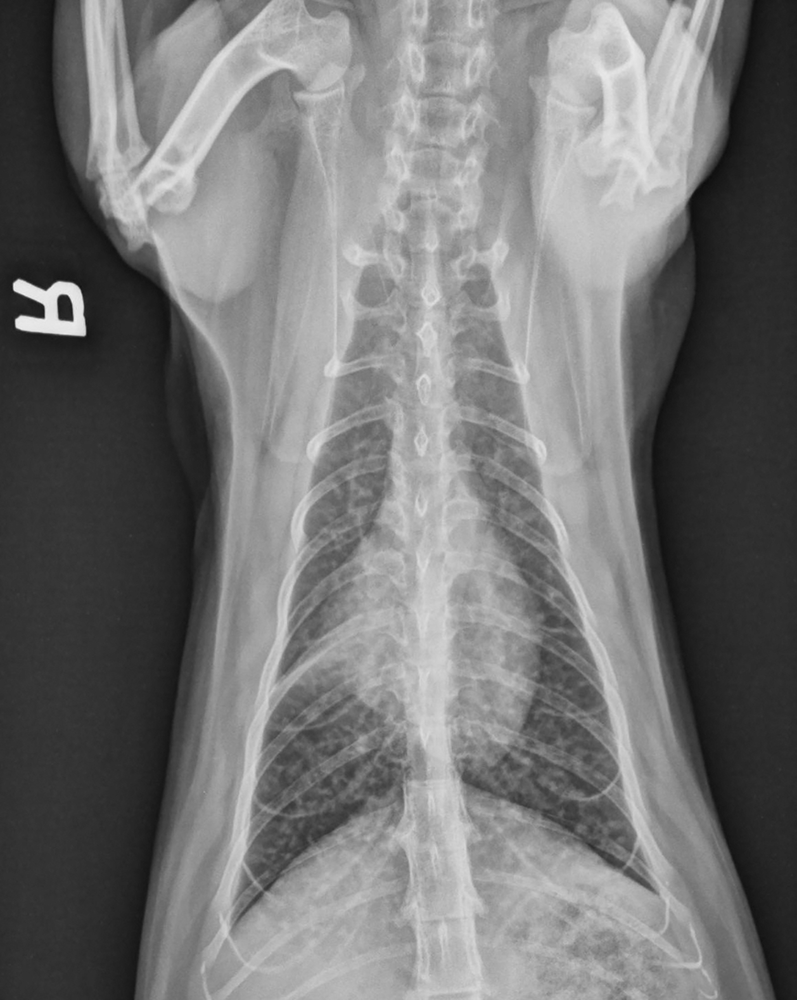

From www.radiokopvet.co.za

Feline Asthma Radiokop Animal Clinic Differentials For Feline Asthma Although there is some debate about the. asthma is a disease of the lower airways of the lungs that affects between 1 and 5% of cats. feline asthma is associated with airway hyperresponsiveness, airflow obstruction, airway remodeling, and eosinophilic airway. • therapy for feline asthma using glucocorticoids and bronchodilators might be inadequate or contraindicated in some cats. . Differentials For Feline Asthma.